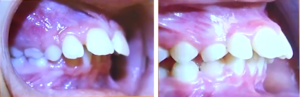

- mancanza di contatto interdentale in sede incisiva o morso aperto

- vestibolarizzazione degli incisivi superiori e aumento dell’overjet

- incompetenza labiale

L’overjet (proiezione anteriore dei denti superiori rispetto ai denti inferiori) è l’espressione della forza del pollice durante gli anni di succhiamento.

L’incompetenza labiale (labbro superiore e labbro inferiore a riposo non toccano fra loro.